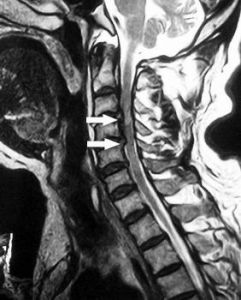

3.MRI(磁共振)檢查

對判定脊髓損傷狀況極有價值。MRI可顯示脊髓損傷早期的水腫、出血,並可顯示脊髓損傷的各種病理變化,脊髓受壓、脊髓橫斷、脊髓不完全性損傷、脊髓萎縮或囊性變等。